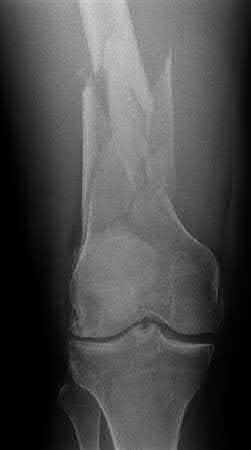

A 38-year-old male suffers the injury shown in Figure A. During operative fixation, free osteoarticular fragments are encountered and reconstruction of these pieces is attempted. Postoperatively, which of the following will have the most beneficial effect on the healing potential of the surviving chondrocytes within these reconstructed articular segments?

Figure A demonstrates a comminuted tibial plateau fracture with significant intra-articular involvement. Basic science evidence has demonstrated that post-operative gentle compressive loading may have a positive impact on articular cartilage healing; however, excessive shear loading may be detrimental.

Irrgang et al provide guidelines for rehabilitation following surgical management of articular cartilage lesions of the knee. They state that after articular cartilage repair, exercises to enhance muscle function must be done in a manner which minimizes shear loading of the joint surfaces in the area of the lesion. The authors also discuss the benefits of gentle compressive loading and motion of the joint, and its positive effects on chondrocyte nutrition.

Furthermore, they recommend a period of protected weight bearing as often being necessary, and that this should be followed by progressive loading of the joint.